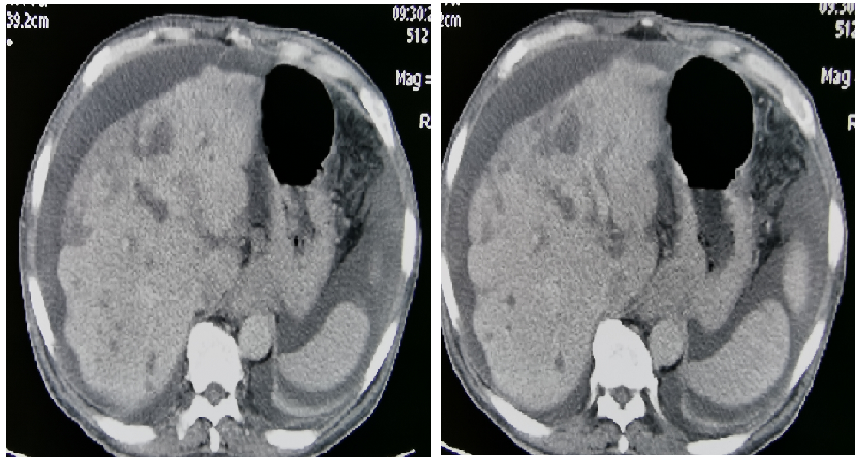

发病后CT(外院2017.11):贲门胃底部溃疡性肿物考虑恶性,腹腔多发肿大淋巴结,考虑转移。

图表1-1:发病后CT(外院2017.11)

CT(外院2018.05):肝内多发占位,考虑转移;贲门胃底部溃疡性肿物;胃低及胃左动脉多发肿大淋巴结;考虑转移。

图表1-2:CT(外院2018.05)